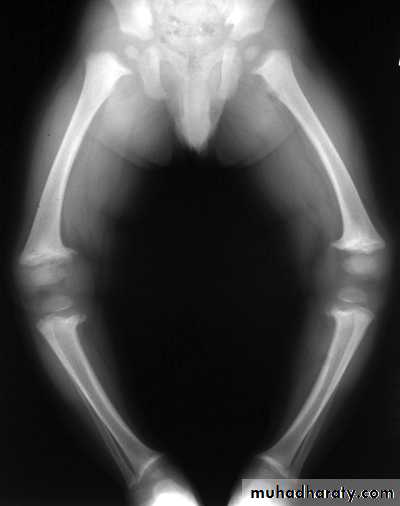

In rickets the changes are maximal where bone growth is occurring , so they are best seen at the knee, wrist and ankle .seen as

. Deficient the zone of provisional calcification .

.widening with irregularly mineralized metaphyses with cupping

.increase distance between the visible epiphysis & the calcified portion of the metaphysis .

.generalized decrease in bone density .

. Deformities of the bones occur because the under mineralized bone is soft , green stick fractures are common .